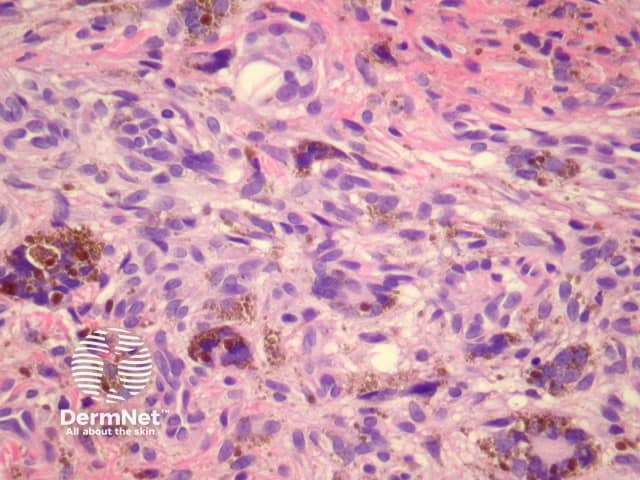

The clinical presentation of aneurysmal dermatofibroma is a rapidly growing blue-brown nodule. Periods of rapid growth are secondary to haemorrhage into the lesion. These tumours have a high recurrence rate and there is a report of aneurysmal dermatofibroma with regional lymph node involvement.

Histologically, there are cleft-like haemorrhagic spaces within the centre of the aneurysmal dermatofibroma that mimic vessels but lack an endothelial lining. The tumour itself tends to be fairly cellular (figure 7, 8). Haemosiderin deposition may be an additional feature. Aneurysmal dermatofibroma may be mistaken for a vascular tumour, however, clues to the diagnosis include surrounding features of dermatofibroma, and endothelial cell markers are positive in normal vessels only and not the aneurysmal spaces.

Figure 7

Figure 8